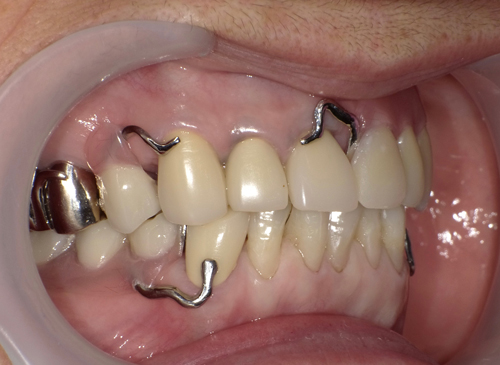

大阪市内より20代の女性。主訴は「2ヶ月前、左下の歯を抜いた。麻酔が効いていないのに抜歯を続けられた。

歯のない所はインプラントにしようと思っている。前歯も綺麗にしたい。痛みや怖いのはゴメンなので、静脈麻酔鎮静で治療をしてもらいたい。」でした。

左下のインプラント予定部。

左下の施術終了。

施術より3ヶ月後、インプラント完成。

適合の良くなかった前歯もセレックを使って、オールセラミックスに順次やり変え。